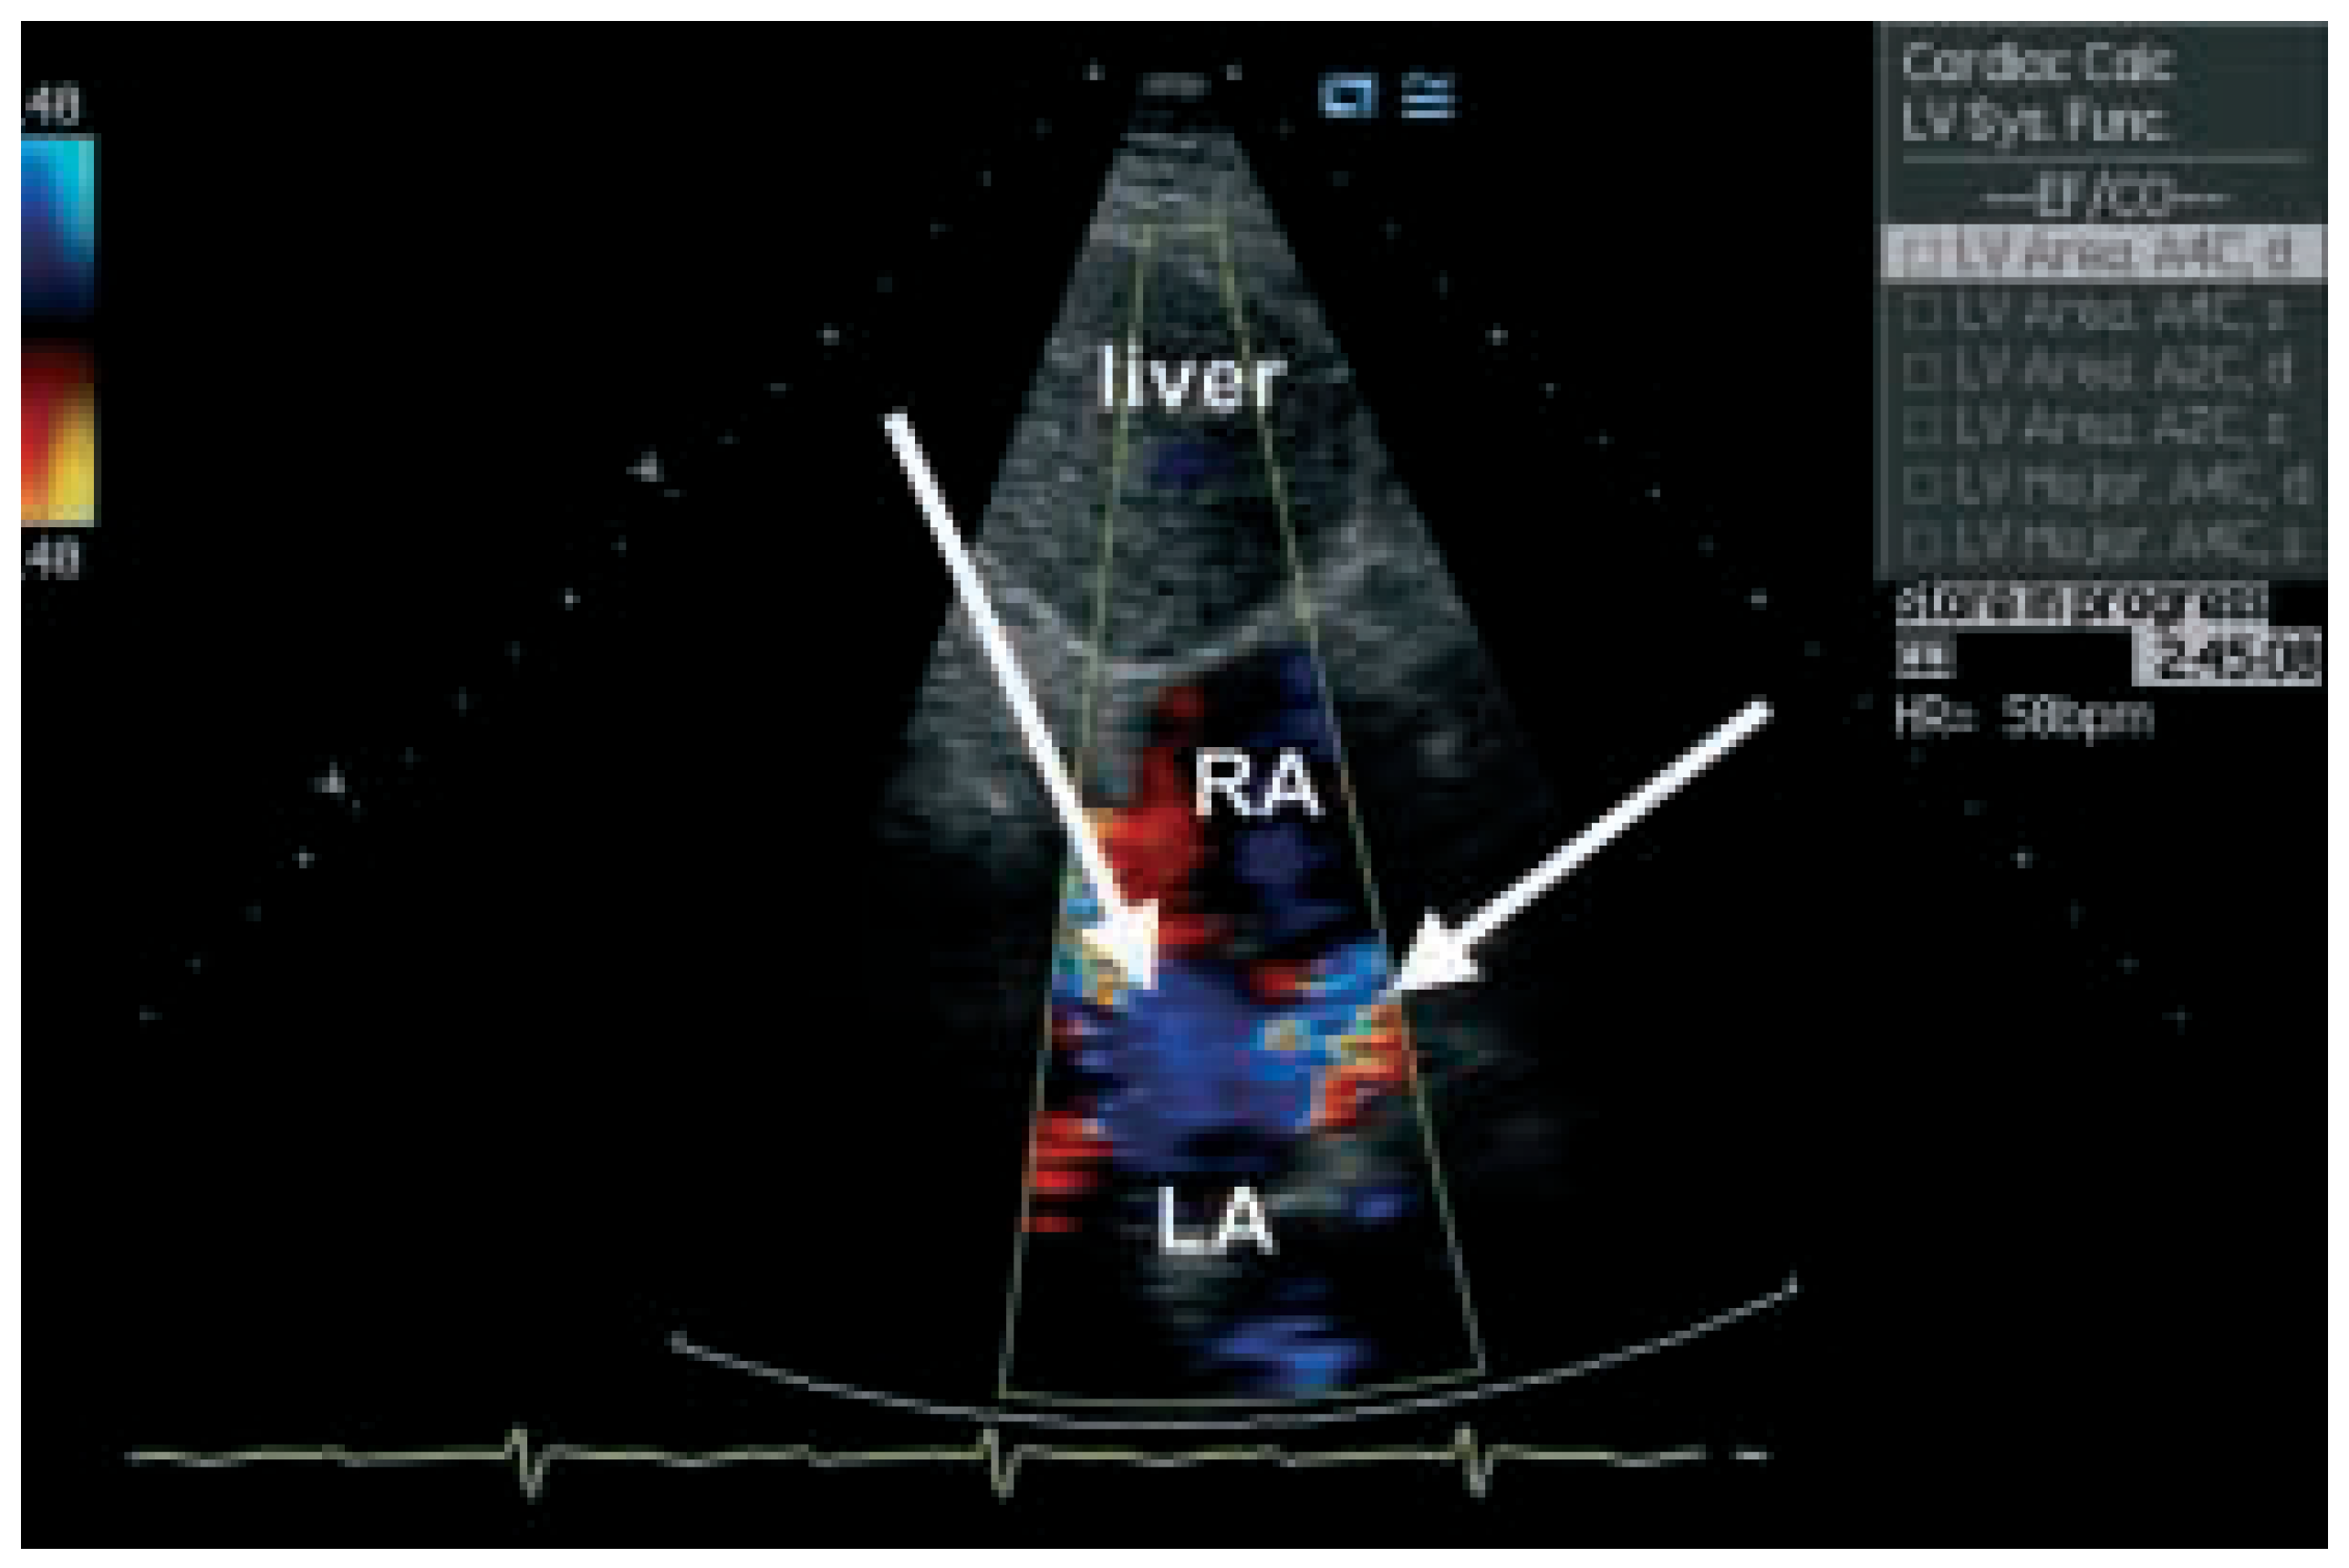

Transthoracic echocardiography (Figure 4 and Figure 5) is not normal and shows right heart overload with dilatation of the right sided cavities, elevated pulmonary artery pressure (estimated systolic pulmonary pressure about 56 mm Hg) and normal sized left ventricle. The reason for the dilatation of the right sided cavities was found in the presence of two secundum atrial septal defects with predominantly left-to-right shunting. Transoesophageal echocardiography was not performed.

Figure 5. Echocardiography: subcostal view with the 2 secundum atrial septal defects (arrows). RA = right atrium; LA = left atrium.